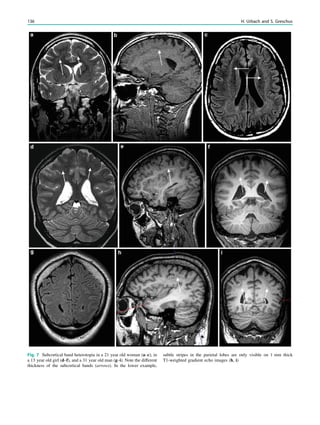

using magnetic resonance (MR) scanners with a magnetic

field strength B0 of at least 1.5 Tesla. Theoretically and in

clinical practice however, 3 Tesla scanners have advantages.

2 Theoretical Considerations

In accordance with the increasing number of parallel spins at